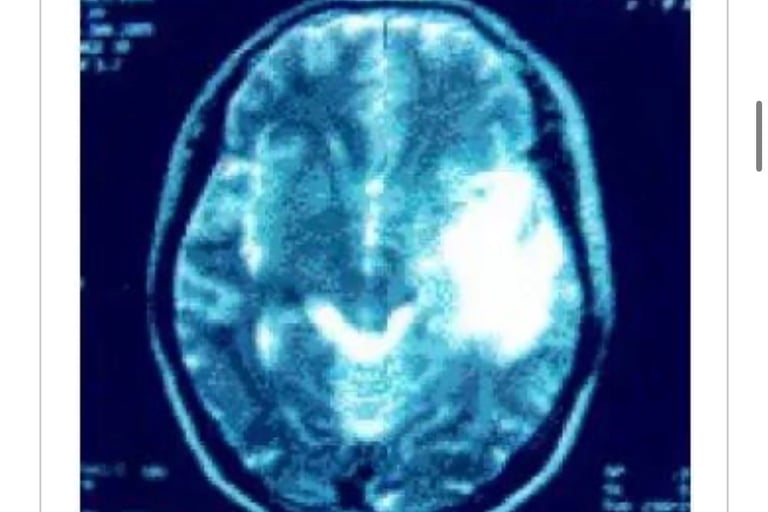

上咽喉癌/颅内转移(2002.3⇒2010.11)

05年1月19日在脑外科被确诊左颞叶、顶叶、侧头均有转移(照片1)医生建议手术。

征得患者同意后。即于2005年1月20日开始,1天2次连续3天实施MW微波照射。之后11月、12月合计14次照射后,患者的癌症活性反应消失。

2006年1月27日的脑MRI显示肿瘤消除(照片2)。